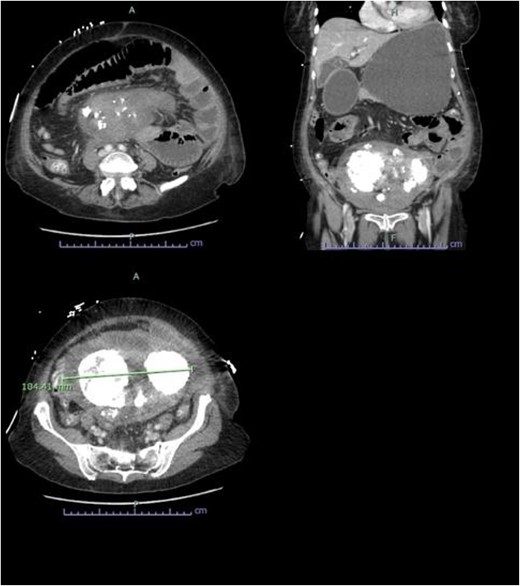

An abdominopelvic CT was performed, which demonstrated evidence of a small bowel obstruction with evidence of extrinsic compression by a gravid uterus at the level of the duodenojejunal flexure (Fig. 1). The mesentery adjacent to the loop of jejunum was associated with mild stranding, however there was no evidence of pneumatosis, or portal venous gas. Bilateral aspiration pneumonia was also demonstrated on CT.

Abdominopelvic CT findings of a large multifibroid uterus with amorphous central calcification associated with a small bowel obstruction.